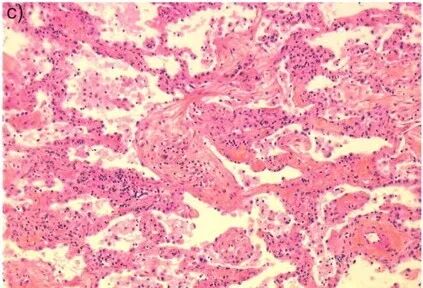

3. 病理特点

OP病变呈斑片状分布,病变中央是小气道;肺泡内、肺泡管见疏松的胶原样的结缔组织增生,形成Masson小体;肺泡内见肺泡巨噬细胞,部分肺泡巨噬细胞呈泡沫状,Ⅱ型肺泡上皮细胞化生。

图片

注:肺泡内的纤维灶称为Masson小体,光镜下表现为同心圆排列的纤维母细胞及肌纤维母细胞,呈息肉样。

在周围的肺泡间隔存在以单核细胞、淋巴细胞浸润为主的炎性渗出,肺泡间隔增厚,可伴或不伴终末和呼吸性细支气管内结缔组织肉芽栓的形成;肺结构往往正常;镜下病变均匀一致。

注:肺泡内、肺泡管、呼吸性细支气管及终末细支气管腔内有息肉样肉芽组织形成。

肺泡腔内肉芽组织呈芽生状,由疏松的结缔组织将成纤维细胞包埋而构成,可通过肺泡孔从一个肺泡扩展至邻近的肺泡,形成典型的“蝴蝶影”。

注:典型的蝴蝶样肺泡内肉芽组织。